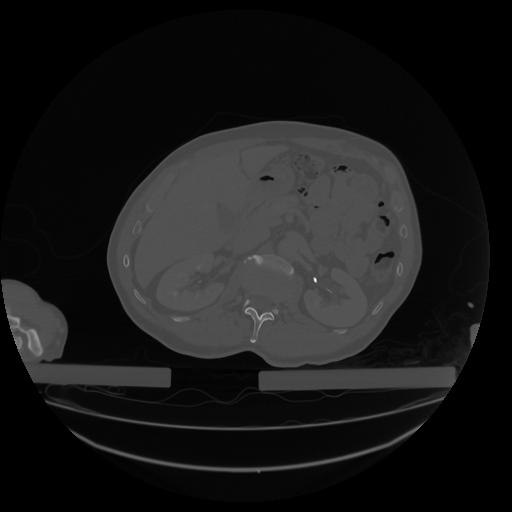

34 CUERPO,CE,Vol,1.0,CUERPO,,